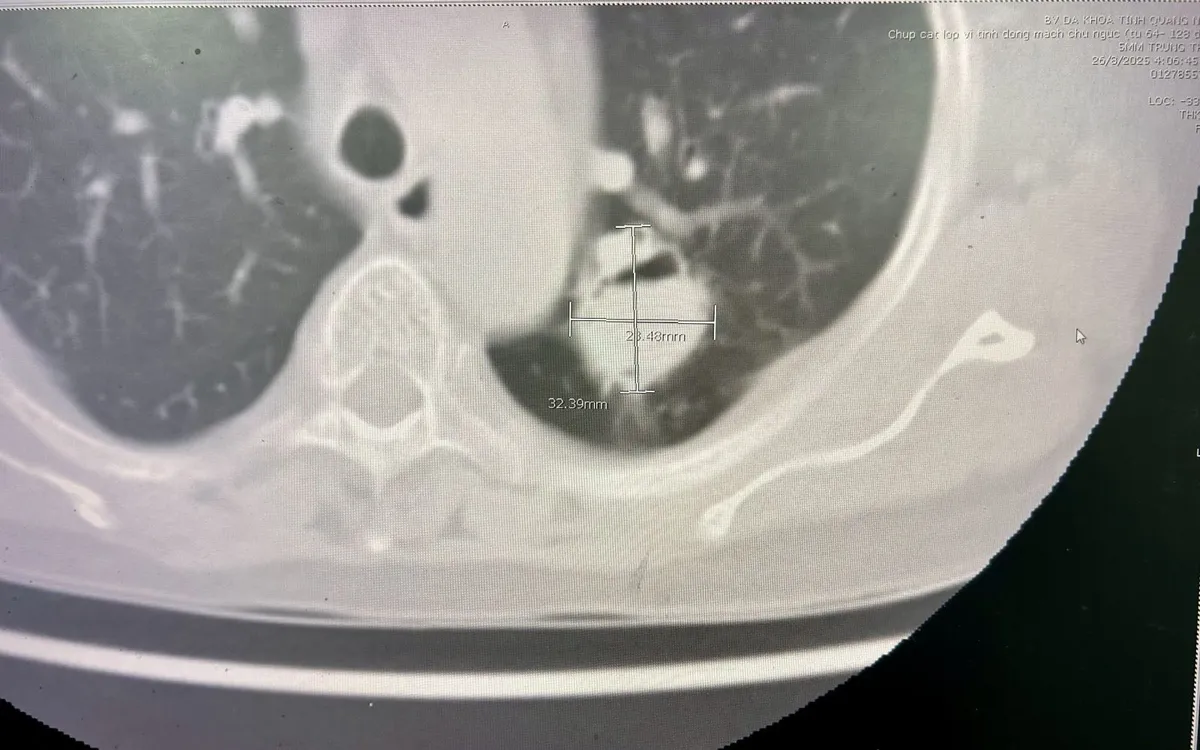

Trong ca mổ, khối u kích thước hơn 3cm nằm sát rốn phổi, dính nhiều vào thùy dưới, thành ngực và động mạch chủ, khiến việc bóc tách trở nên phức tạp. Sau hơn 2 giờ, ekip phẫu thuật đã cắt trọn thùy phổi chứa u nấm, bảo tồn phần phổi còn lại, đảm bảo thông khí tốt.